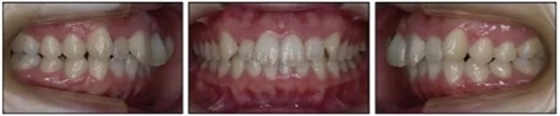

一、患者信息

1.基本信息:女性,24歲2月,主訴上前牙及上唇不美觀(圖1)。因美觀問題不愿使用上頜固定矯治器。

2.檢查:凸面型、骨性II類,安氏II類1分類錯(cuò)合畸形。面型正中對稱,下面高略高,頦部后縮,唇肌略緊張。無顳下頜關(guān)節(jié)癥狀,下頜運(yùn)動正常,無偏斜。上下頜中線與面中線相一致,所有恒牙存在,口腔衛(wèi)生可,牙周情況可?;颊呓】?,無系統(tǒng)性疾病,無牙科創(chuàng)傷史及不良習(xí)慣,懷疑遺傳因素導(dǎo)致錯(cuò)合畸形。

3.測量分析:治療前記錄提示該患者左右磨牙與尖牙為安氏II類關(guān)系,上頜牙弓重度擁擠,下頜牙弓輕度擁擠,深Spee曲線。6.3mm深覆蓋,80%深覆合。牙齒無齲,無第三磨牙。